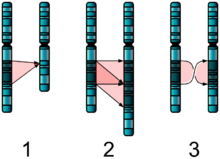

Autism has a strong genetic basis, although the genetics of autism are complex and it is unclear whether ASD is explained more by rare mutations with major effects, or by rare multigene interactions of common genetic variants. Complexity arises due to interactions among multiple genes, the environment, and epigenetic factors which do not change DNA but are heritable and influence gene expression. Studies of twins suggest that heritability is 0.7 for autism and as high as 0.9 for ASD, and siblings of those with autism are about 25 times more likely to be autistic than the general population. However, most of the mutations that increase autism risk have not been identified. Typically, autism cannot be traced to a Mendelian (single-gene) mutation or to a single chromosome abnormality, and none of the genetic syndromes associated with ASDs have been shown to selectively cause ASD. Numerous candidate genes have been located, with only small effects attributable to any particular gene. The large number of autistic individuals with unaffected family members may result from copy number variations—spontaneous deletions or duplications in genetic material during meiosis. Hence, a substantial fraction of autism cases may be traceable to genetic causes that are highly heritable but not inherited: that is, the mutation that causes the autism is not present in the parental genome.

In the genetic area, relations have been found between autism and schizophrenia based on duplications and deletions of chromosomes; research showed that schizophrenia and autism are significantly more common in combination with 1q21.1 deletion syndrome. Research on autism/schizophrenia relations for chromosome 15 (15q13.3), chromosome 16 (16p13.1) and chromosome 17 (17p12) are inconclusive.

Clinical genetics evaluations are often done once ASD is diagnosed, particularly when other symptoms already suggest a genetic cause. Although genetic technology allows clinical geneticists to link an estimated 40% of cases to genetic causes, consensus guidelines in the US and UK are limited to high-resolution chromosome and fragile X testing. A genotype-first model of diagnosis has been proposed, which would routinely assess the genome's copy number variations. As new genetic tests are developed several ethical, legal, and social issues will emerge. Commercial availability of tests may precede adequate understanding of how to use test results, given the complexity of autism's genetics. Metabolic and neuroimaging tests are sometimes helpful, but are not routine.